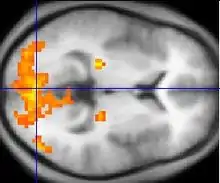

Monochrome fMRI image of a horizontal cross-section of a human brain. A few regions, mostly to the rear, are highlighted in orange and yellow.

Functional magnetic resonance imaging provides some evidence for mirror neuron theory.[79]

Asperger syndrome appears to result from developmental factors that affect many or all functional brain systems, as opposed to localized effects.[80]

Mirror neuron system (MNS) theory

The mirror neuron system (MNS) theory hypothesizes that alterations to the development of the MNS interfere with imitation and lead to Asperger's core feature of social impairment.[79][86] One study found that activation is delayed in the core circuit for imitation in individuals with AS.[87] This theory maps well to social cognition theories like the theory of mind, which hypothesizes that autistic behavior arises from impairments in ascribing mental states to oneself and others;[88] or hyper-systemizing, which hypothesizes that autistic individuals can systematize internal operation to handle internal events but are less effective at empathizing when handling events generated by other agents.[89]